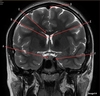

Image weighting and axis

T2 Axial

A

Basal Ganglia

B

Posterior horn lateral ventricle